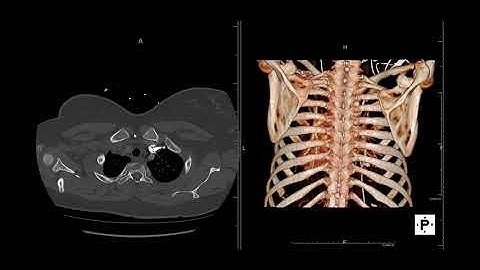

Introduction to CT Chest - Anatomy and Approach